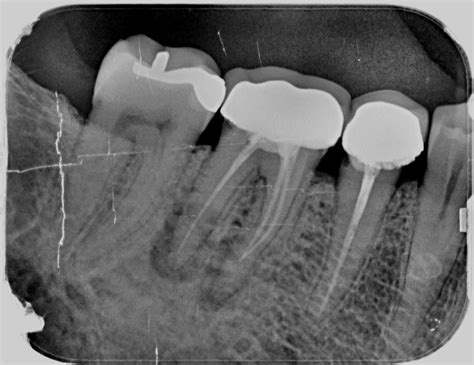

- Evaluación profesional: El primer paso que debes seguir si sospechas que tu endodoncia ha fracasado es pedir cita con un dentista con experiencia en endodoncia o en cirugía bucal para evaluar la situación. Diagnosticar una endodoncia fracasada requiere una evaluación detallada por parte de un profesional. El dentista evalúa los síntomas que presenta el paciente y realiza una radiografía y una tomografía para observar el diente y los tejidos de alrededor.

- Evaluación y preparación: Primero confirmamos, mediante radiografías y pruebas clínicas, que la reendodoncia es la mejor opción. En esta fase previa tomamos radiografías periapicales y, si es necesario, escáner 3D (TAC) para ver la anatomía completa de los conductos y localizar posibles problemas (como un conducto oculto o una fractura radicular). Planificamos el retratamiento identificando la causa del fallo de la primera endodoncia.